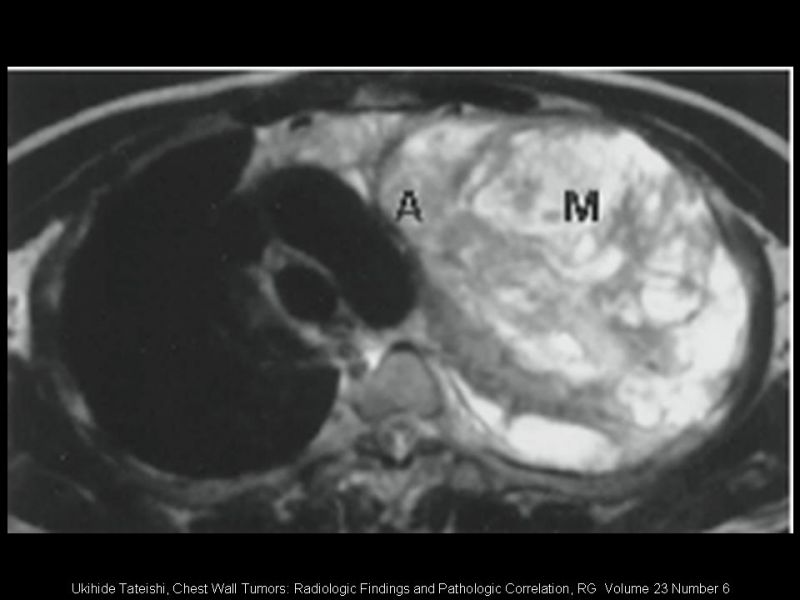

Tumores Primarios de Pared Torácica

Cirugía Torácica

| Autor: Dr. Rodrigo Subiabre F, MBA